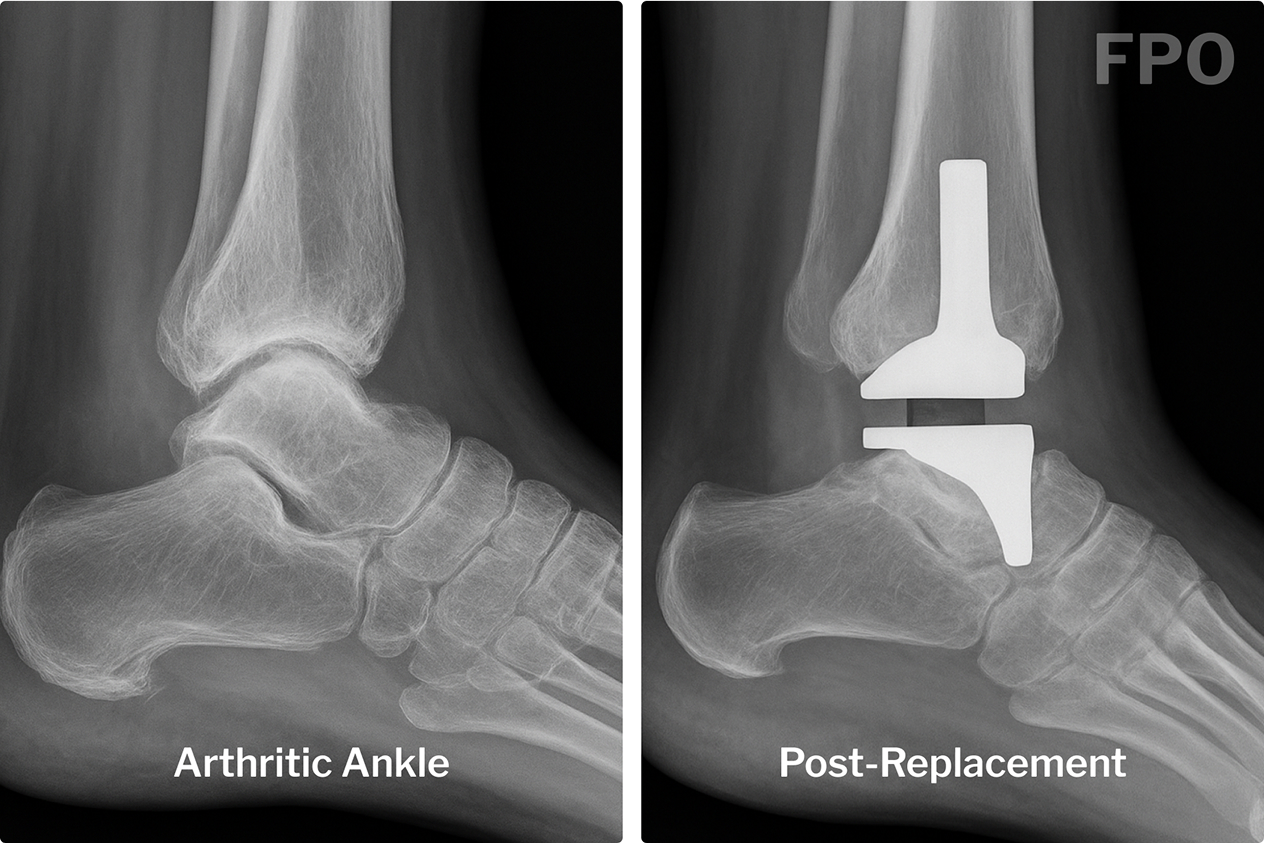

What Is Total Ankle Replacement?

Total Ankle Replacement (TAR), also called ankle arthroplasty, involves replacing the damaged parts of the ankle joint with metal and plastic components that mimic natural motion.

The goal?

- Reduce pain

- Restore movement

- Help you return to the activities you love